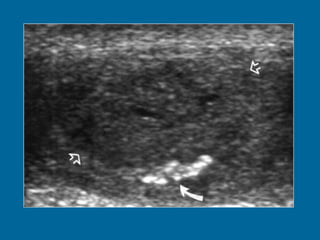

Figure 7. Sertoli cell tumour. Large smooth curvilinear calcification (curved arrow) at the periphery of a heterogeneous mass (open arrows).

Figure 7. Sertolicell tumour. Large smooth curvilinear calcification (curved arrow) at the periphery of a heterogeneous mass (open arrows).